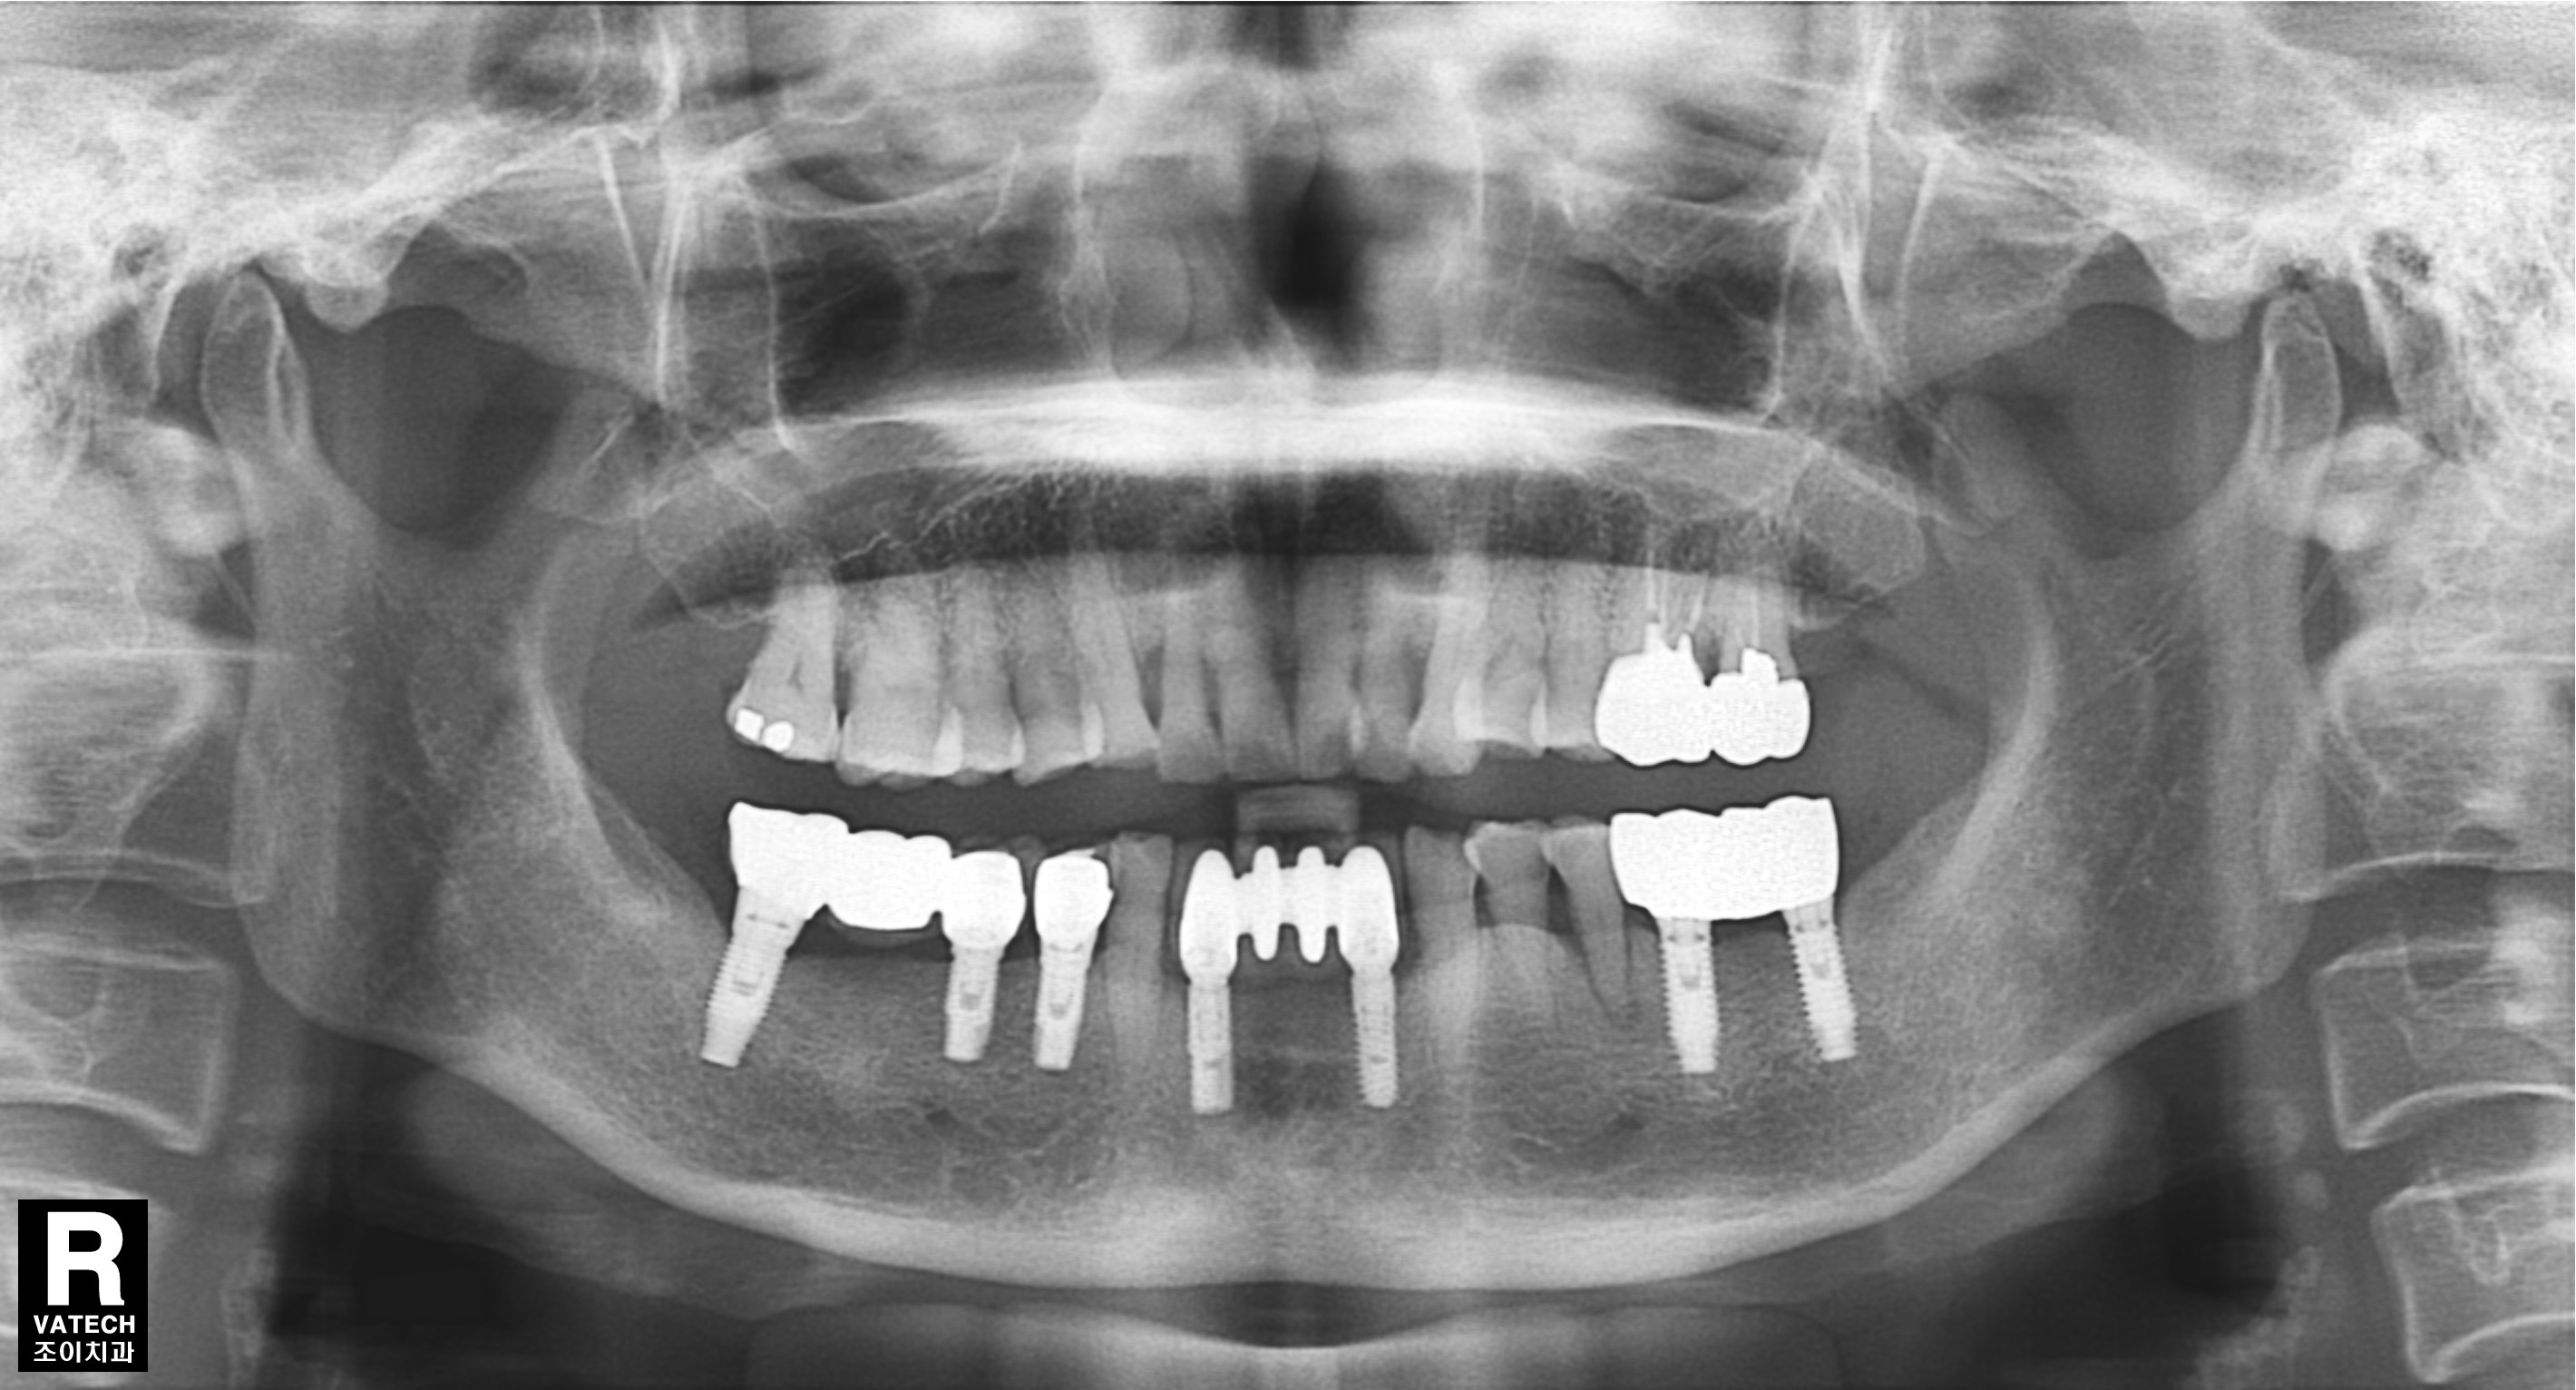

임플란트 보철. 조이치과에서는 임플란트 시술 후 관리를 위하여 보철물 위에 스크류홀을 형성하는 SCRP보철을 주로 이용합니다.

SCRP를 만들기 위해서는 정확한 임플란트가 정확한 위치와 경사로 심겨져야합니다.